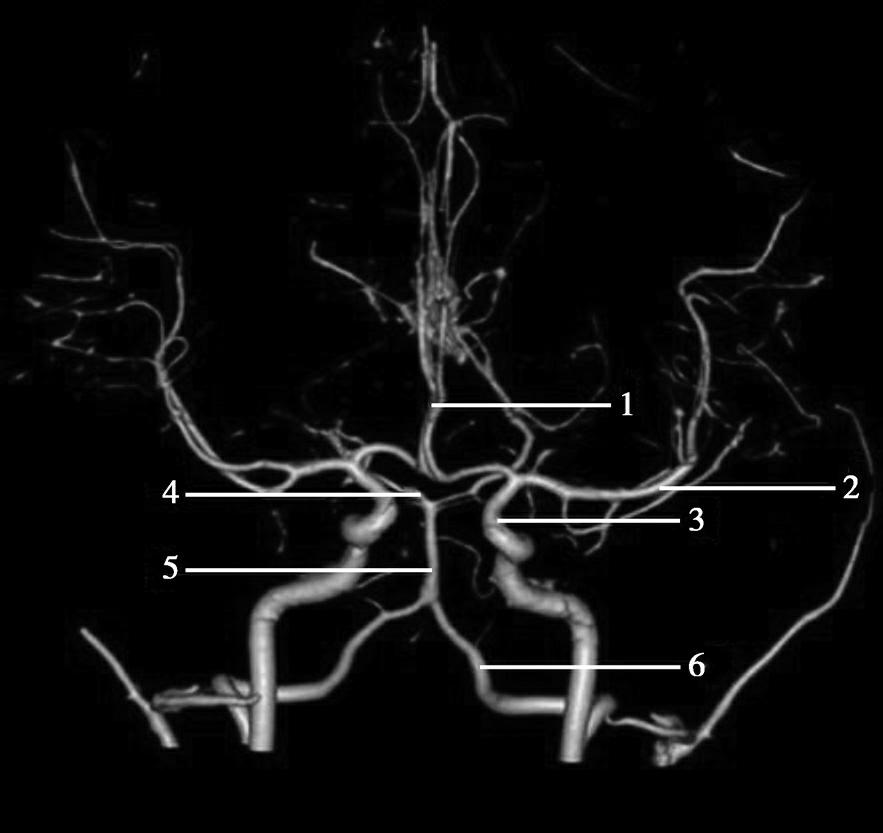

CT血管成像(CT angiography,CTA及CT venography,CTV)通过三维重建技术可显示颅内动静脉的走行、血管壁及血管周围等情况(图1-2-73~图1-2-75)。

图1-2-73 正常颅脑CTA

1.大脑前动脉;2.大脑中动脉;3.颈内动脉;4.大脑后动脉;5.基底动脉;6.椎动脉